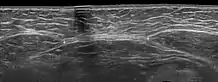

Существуют различные подходы к диагностике диастаза. В большинстве случаев диагноз можно поставить клиническим путем, не прибегая к дополнительным инструментальным методам. При этом бывает достаточно осмотра, пальпации и простых измерений. Иногда, особенно в научных целях, используют дополнительные инструментальные и аппаратные методы, например УЗИ (ультразвуковое исследование) или КТ (компьютерная томография).

Ультразвуковое исследование может потребоваться в отдельных случаях, например при наличии избыточного веса у пациентки, когда осмотр и пальпация не дают однозначной четкой картины. УЗИ хорошо видит слои передней брюшной стенки и позволяет точно измерить ширину диастаза на разных уровнях.